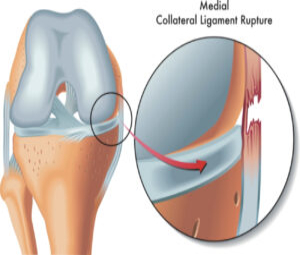

Phục hồi chức năng bệnh lý cơ xương khớp